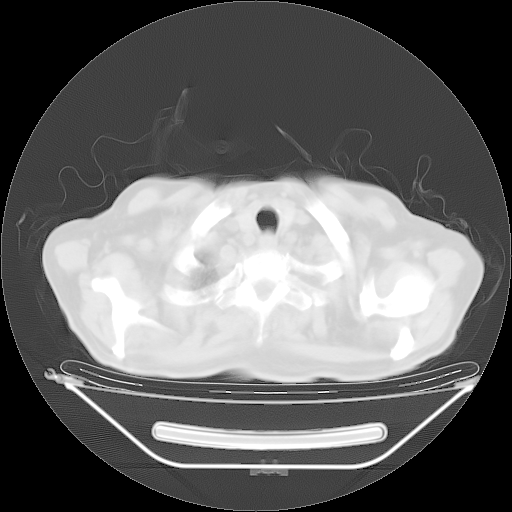

5月9日肺部CT(在4月27日齐鲁医院肺部CT描述部分肺组织磨玻璃样改变,12天后肺组织广泛磨玻璃样改变)

2009年5月9日肺部CT

大致读了系列胸部CT:纵隔窗无明显异常,肺窗:从4、27至今:主要是双肺中下野外带可见毛玻璃样改变,目前处于急性肺泡炎阶段,至于原因考虑1、结替组织或胶原血管性疾病所致?2、恶性疾病如恶组在肺部所致的表现或细支气管肺泡癌?3、药物或其它原因如肺蛋白沉着症所致肺泡炎目前不太可能?总之,明天就去请我院的呼吸科、感染科、血液科和临免专家会诊哈。